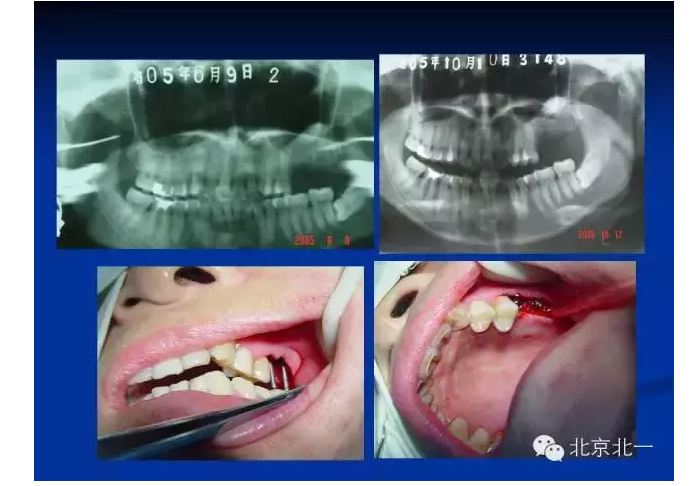

擅長(zhǎng):種植外科,尤其專長(zhǎng)復(fù)雜牙種植,自體骨移植同期種植,上頜竇底內(nèi)外提升同期種植技術(shù),美學(xué)區(qū)種植技術(shù),即刻種植外科與即刻負(fù)重技術(shù),軟組織成形外科種植技術(shù)及全口無牙頜ALL-ON-FOUR技術(shù),種植并發(fā)癥和種植急癥處置等手術(shù)治療,從事口腔頜面外科,正頜外科、頜面部整形、微創(chuàng)拔牙,笑氣無痛舒適種植十余年。